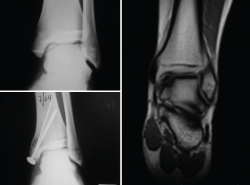

Patients with osteochondral defects of the ankle: results of the first patients with two years of follow-up

A study was made of the first 52 patients with osteochondral defects of the ankle treated with the ICC technique - most of them (34 patients) in the Clínica CEMTRO(35). One of the particularities of the chondrocyte implant procedure in the ankle is that in most cases an osteotomy is first required in order to access the lesion. Although in some patients the defect was more superficial, in the majority of cases (up to 96%) the defect was of an osteochondral nature. In 35% of the patients the lesion was over 4 mm in depth, and a cancellous bone graft was required, obtained from the osteotomy itself, above the subchondral bone, with placement of the membrane with the cells over this graft.

The short/middle term outcomes of the treated patients were very satisfactory. Both pain, evaluated by means of the VAS, and ankle function assessed by the American Orthopedic Foot and Ankle Society (AOFAS) score(36), improved significantly one year after treatment, and this improvement persisted at least one year later. The percentage of patients with good or excellent outcomes after 12 months was 75%, and this figure further increased to 79.2% at 24 months post-treatment.

[[{"fid":"4553","view_mode":"default","fields":{"format":"default","alignment":""},"type":"media","field_deltas":{"22":{"format":"default","alignment":""}},"link_text":null,"attributes":{"class":"media-element file-default","data-delta":"22"}}]]

The clinical results were correlated to the radiological findings, revealing correct graft integration and regeneration of the cartilage (Figure 19).